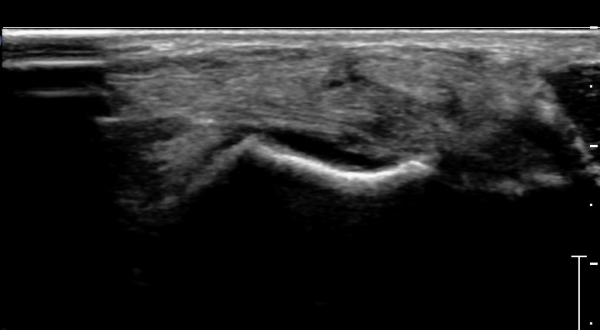

Àü°ÅºñÀδë ÇϺΠÁ¾´Ü¸é°Ë»ç¿¡¼­ Àü°ÅºñÀδëÀÇ Àú¿¡ÄÚ À§Ãø°ú Á·±Ùµ¿ÀÇ ¼ö¾×Àú·ù°¡

°üÂûµÈ´Ù(»çÁø 2, 3, 4).